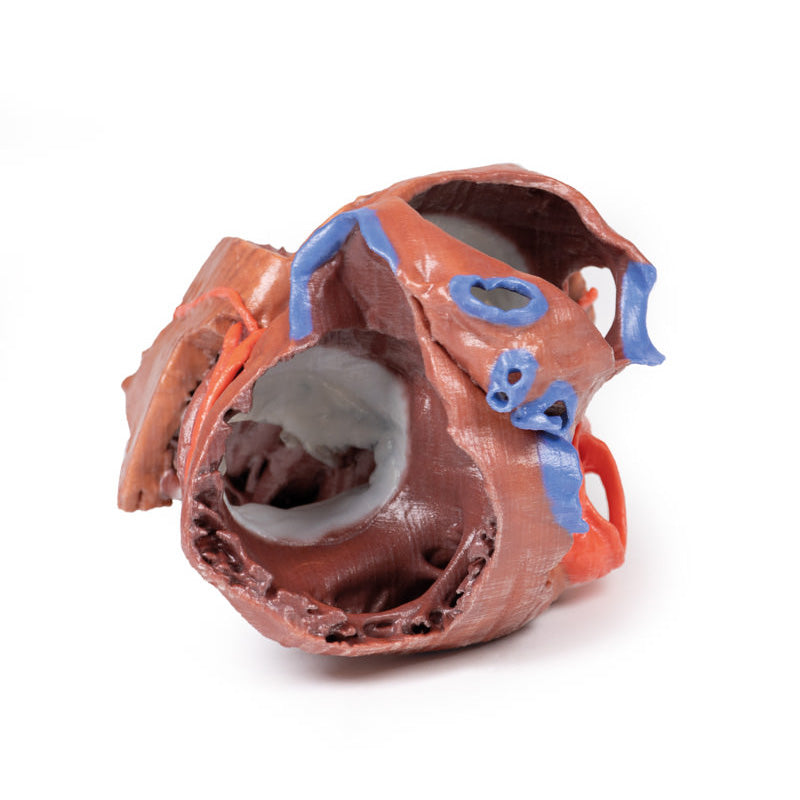

On the posterior side of heart the terminations of the pulmonary veins are visible entering the opened left atrium. Just anterior to the depression of the fossa ovalis in the interatrial septum the left atrioventricular valve with its two cusps (anterior and posterior) is preserved, along with the associated chordae tendineae and papillary muscles in the ventricle.

On the posterior side of heart the terminations of the pulmonary veins are visible entering the opened left atrium. Just anterior to the depression of the fossa ovalis in the interatrial septum the left atrioventricular valve with its two cusps (anterior and posterior) is preserved, along with the associated chordae tendineae and papillary muscles in the ventricle.